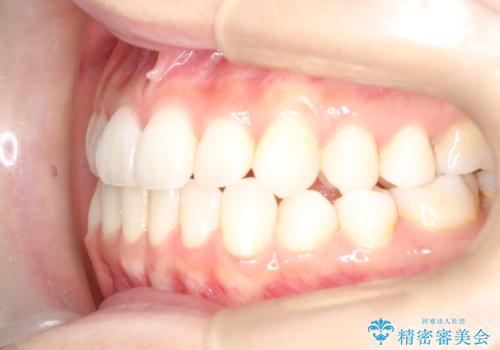

軽度の前歯のガタガタをインビザラインでの目立たない矯正

- 前歯のガタガタを主訴に来院されました。

軽度であったため、枚数制限のあるタイプのインビザラインのプランで治療することとしました。

軽度のガタガタを目立たずに手軽に矯正できるのもマウスピース矯正の魅力といえます。